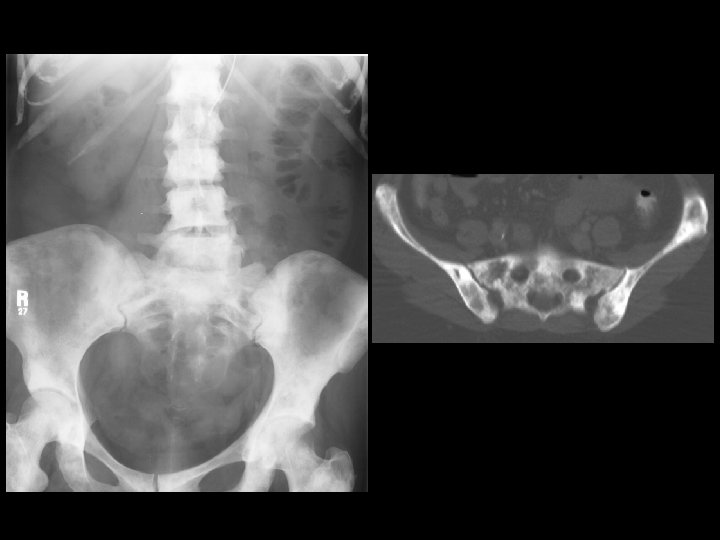

Prostate metastases • Findings: – Diffuse sclerosis • ddx: – Breat, GI mets – myelofibrosis – renal osteodystrophy – osteopetrosis – multiple myeloma